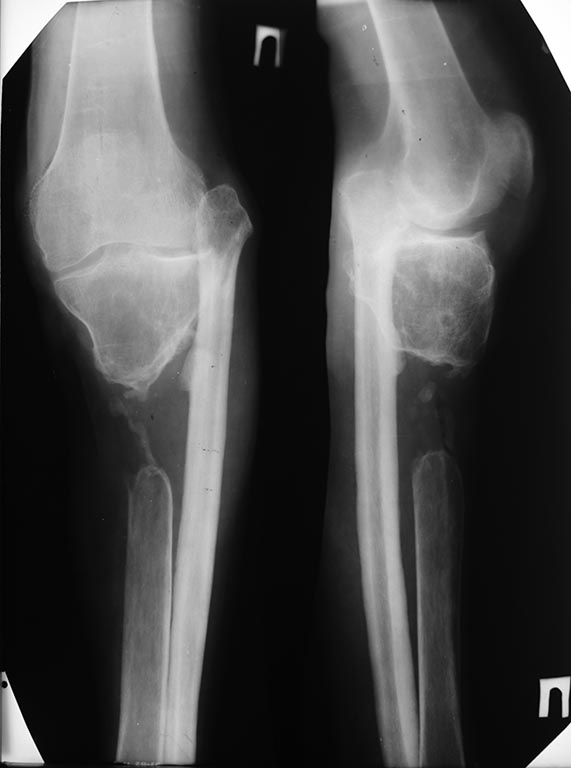

Травма времен Великой Отечественной войны, огнестрельный перелом, дефект большеберцовой кости.

Рентгенограмма 1985 года. В это время пациент передвигался с тростью с практически полной нагрузкой на ногу. Малоберцовая перестроилась под нагрузкой. Проксимальное межберцовое сочленение просело. Движения в "коленном суставе" до 10 градусов.